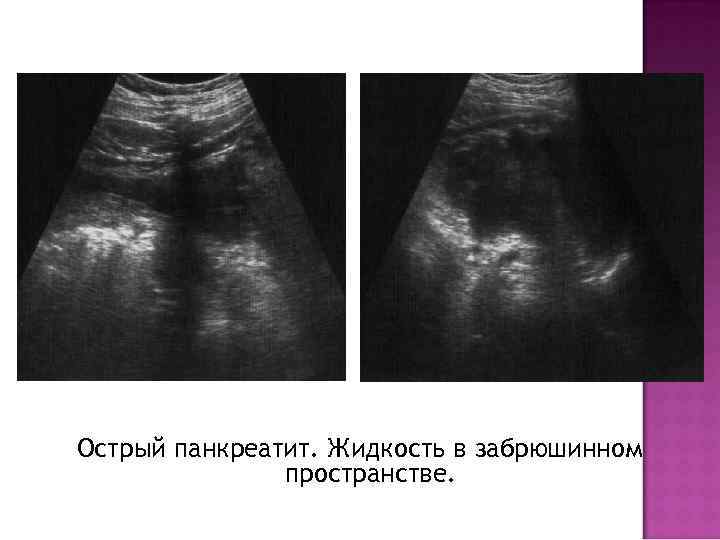

Острый панкреатит. Жидкость в забрюшинном пространстве.